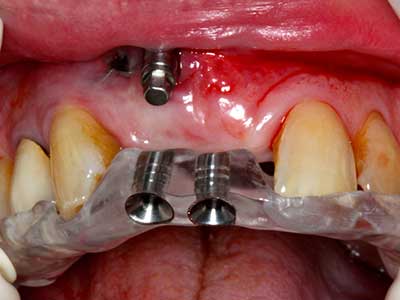

When surgical procedures are performed on bone in the immediate vicinity of sensitive structures such as blood vessels or nerves, rotary instruments pose a significant risk of iatrogenic injury. Piezoelectric devices can be helpful for preparation of bone covers and removal of hard tissue close to nerves, particularly for exposure of nerves after iatrogenic injury but also during nerve lateralization for resective and reconstructive procedures or implant placement (Fig. 17-20). Light contact between the piezotip and the nerve does not generally result in damage but proceeding incautiously with saw-like motions or attachments where a residual bone substrate remains may cause temporary or even permanent nerve damage. However, the risk of damage is considered to be substantially lower than when using saws or milling instruments (Pereira, Gealh et al. 2014).